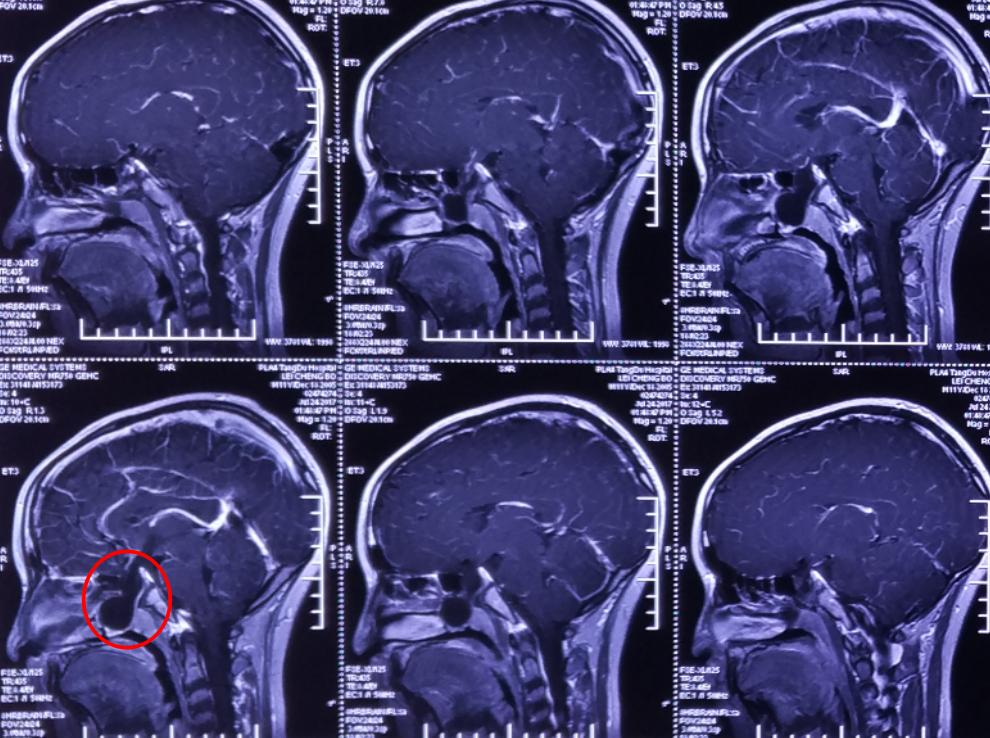

影像资料

术后影像